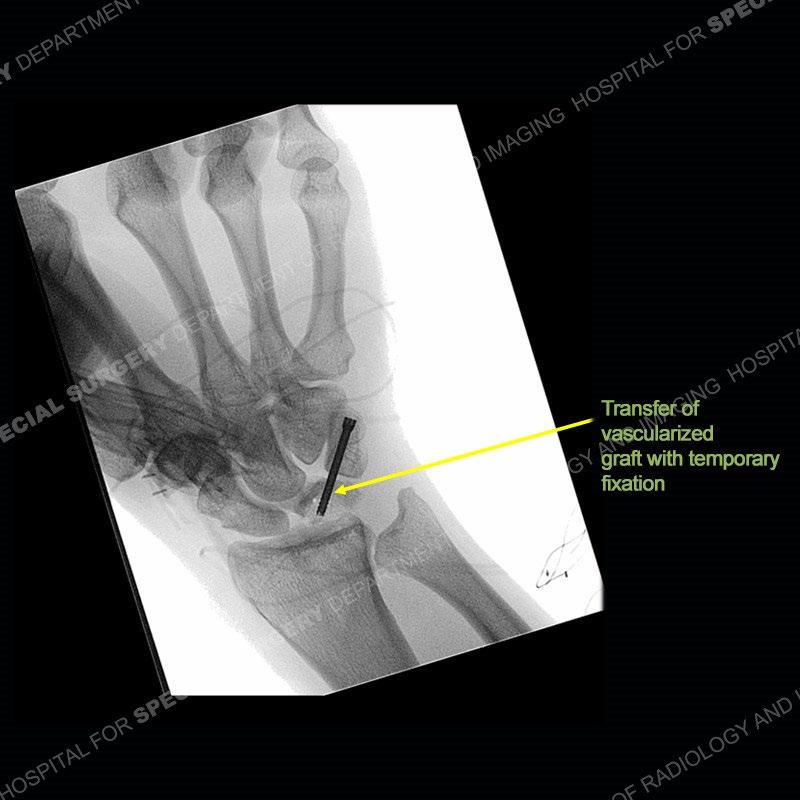

The treatment as the underlying cause of Kienbock’s remains somewhat elusive. Prior to collapse, osteotomies to decrease load or shearing forces to the lunate may be helpful. Once collapse and arthritis have been engendered, fusion and carpectomy have been performed. Now, the role for vascularized bone grafting is being investigated with long term results still being somewhat lacking. Given the young age of the second patient and lack of adjacent, advanced cartilage wear, a vascularized bone graft was performed. The area of necrotic bone was excised, a vascularized bone graft from the distal femur was harvested, and then using microsurgical technique it was grafted to the lunate. A temporary fixation was performed and once the graft was incorporated, the fixation hardware was removed. Although still early in the postoperative period, the patient is doing well.